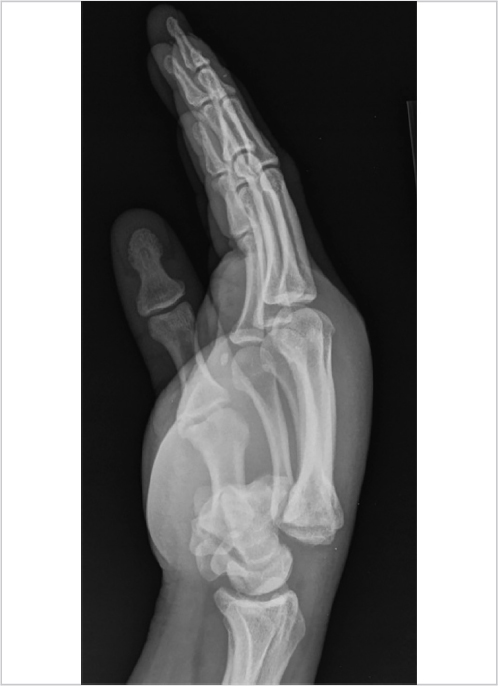

The first CMC joint is unique to humans, allowing opposition and prehension, but hastening the development of arthritic changes. The CMC joint is a biconcave–convex saddle joint, with five articular surfaces and minimal bony constraint. Sixteen ligaments have been described that stabilize the trapezium. Compressive forces magnify greater than 13 times from the fingertip to the trapeziometacarpal joint. Osteoarthritic lesions are first found palmarly on the joint. Degeneration of the posterior oblique ligament has been linked to the development of arthritis when incompetence of the ligament allows abnormal dorsal translation of the metacarpal on the trapezium. 3 The CMC is best viewed by the Roberts technique (thumb AP), where the forearm is maximally pronated and the dorsum of the thumb rests on the X-ray cassette (Fig. 2‑5).